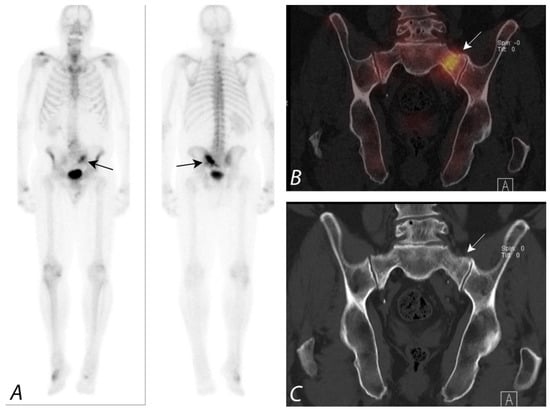

5. Evaluation of Postoperative Spine

6. Hip Pain